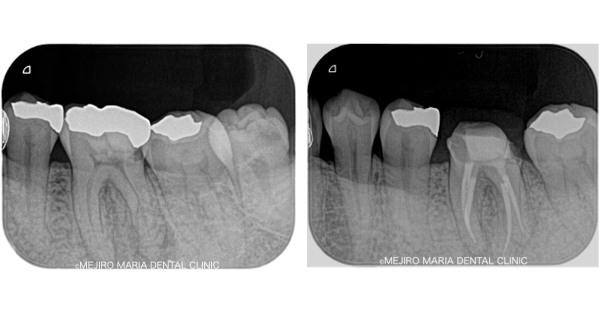

歯科用拡大鏡、歯科用顕微鏡下にて、軟化象牙質(虫歯)を除去後、歯髄を確認すると一部の歯髄には血流がなく部分壊死を起こしていることがわかる。

今回は術前に歯髄炎による疼痛を確認していたため、水酸化カルシウムを貼薬した後、2回目の治療にて根管充填、支台築造処置を終了させている。

|歯の寿命を左右する初回根管治療_術前術後のレントゲン画像比較-1024x756.jpg)